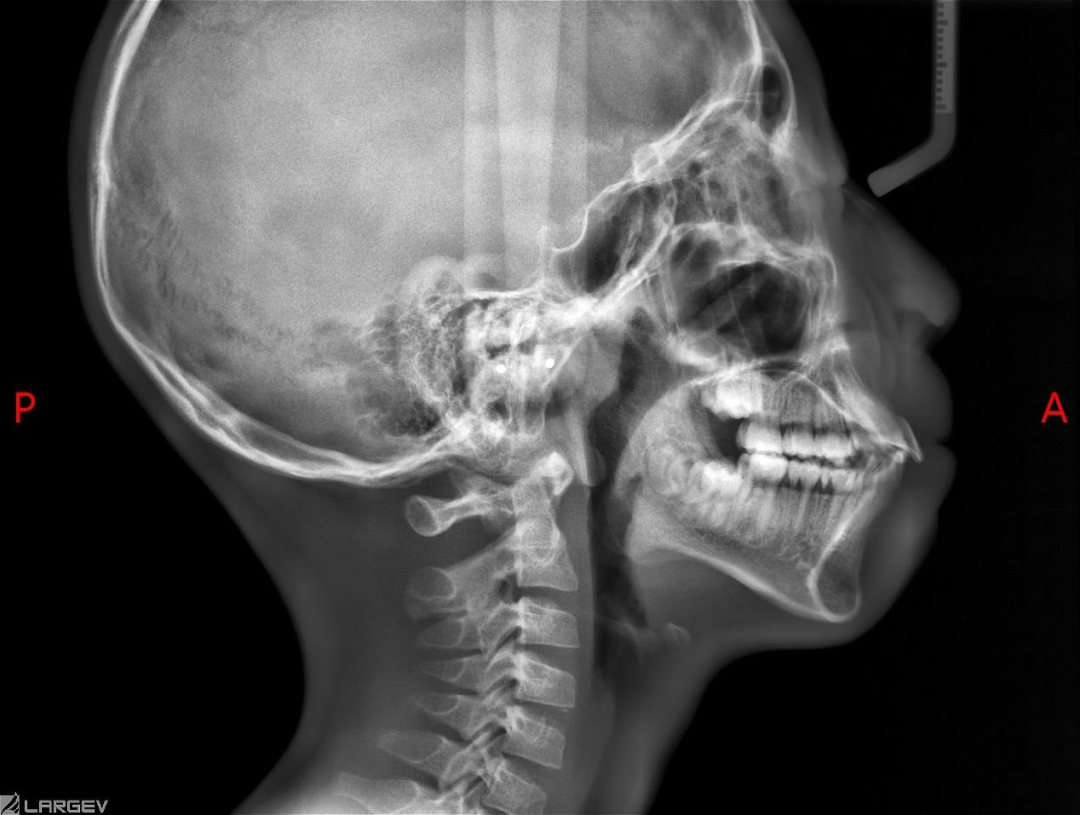

乳牙列期的不良习惯,如吮指、长期使用安抚奶嘴、吐舌吞咽以及口呼吸等,都容易造成前牙开颌、反颌,嘴凸,下巴后缩问题。

这些习惯需要及时干预,以免影响上下颌骨的正常发育,所以家长们在日常生活中需要密切观察孩子的行为,一旦发现不良习惯,可以在4-6岁开始进行干预。

尤其孩子简单的唇舌肌训练坚持不下来,或者对于不良口腔习惯的言语纠正不管用,可考虑采用舌挡、舌刺、肌功能矫治器进行辅助矫正。